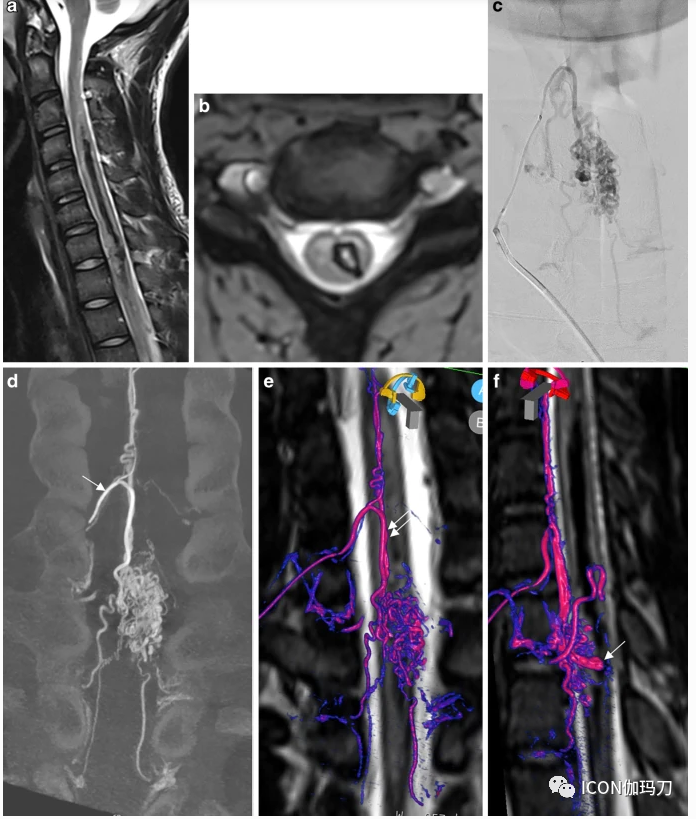

一位青少年因突然左侧偏瘫入院。脊柱MRI显示左侧血肿和位于脊髓内和颈胸交界处的多处血流空洞,提示脊柱动静脉畸形(图3)。DSA证实了这一诊断。颈动脉扩张的根髓动脉(Lazorthes动脉)是造成动静脉畸形的主要原因,它起源于右颈深动脉。另一条起源于上肋间动脉的根髓动脉供应动静脉畸形下部。DSA显示一个位于病灶内侧边缘的4 mm囊状动脉瘤。3DRA和各向同性T2w脊柱MRI融合显示动脉瘤位于脊髓中央部分,动脉瘤尖端位于血肿内(视频2)。在急性期,用线圈对动脉瘤进行靶向栓塞以防止再出血。(DSA前后位投影)。患者的临床恢复情况良好,除了右臂轻微无力外,无其余症状。

3.破裂性脊髓动静脉畸形(AVM)合并大的内动脉瘤。T2W矢状面显示左侧大面积血肿。b血闪显示左侧脊髓内血肿扩大。c (DSA前后位投影)。d(冠状位重组3DRA)超选择性注射颈部肿大的主神经根髓动脉(Lazorthes动脉,箭头),显示一个大病灶和多条引流的神经根静脉。e, f三维旋转血管造影(3DRA)和T2W脊柱磁共振成像(MRI)融合显示供给脊髓根动脉的脊髓前动脉(双箭头),后者供给动静脉畸形(红色/粉色为动脉,紫色或蓝色为引流静脉)。膜内动脉瘤位于髓鞘中心,动脉瘤尖端指向血肿。补充视频演示了融合与嵌入式三维模型的AVM